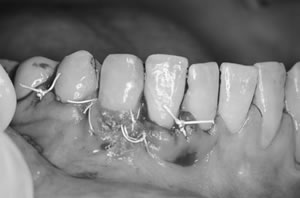

先週は結合組織移植術による根面被覆治療をおこないました。

結合組織移植術による根面被覆治療です。 |